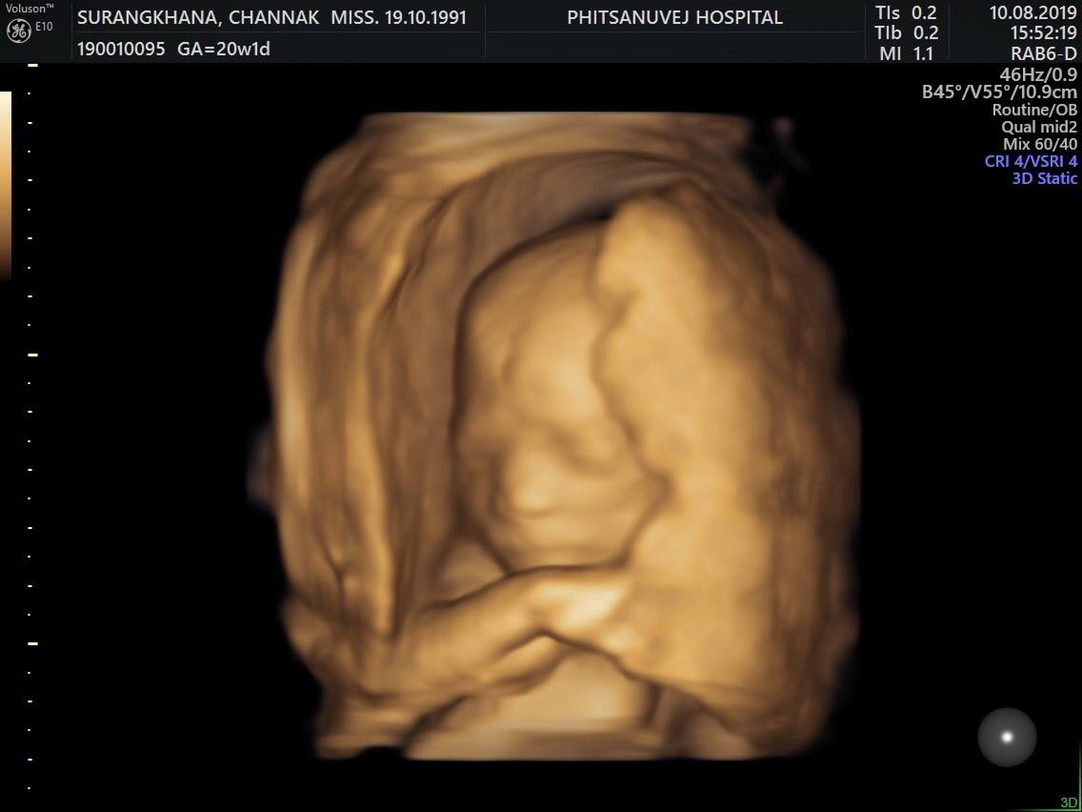

บ้านนี้ได้ลูกสาวค่ะ ตอนนี้ 20+6 W กำหนดคลอด 27 ธ.ค.2562 ท้องแรกค่ะ (รูปตอน20+1W)